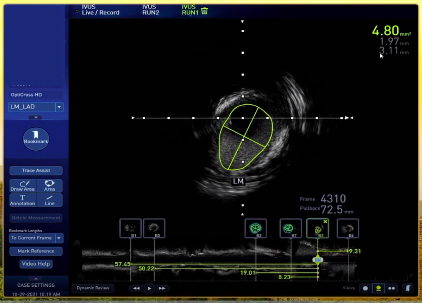

左主干存在偏心斑块,延续至开口上沿,最小管腔面积仅4.8mm²。

左主干IVUS影像特点